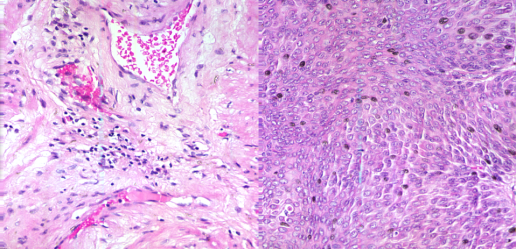

圖2 (a)100X宮頸癌非腫瘤切片 (b)100X宮頸癌腫瘤切片

圖3 左邊:40X膀胱癌非腫瘤切片;右邊:40X膀胱癌腫瘤切片